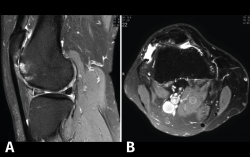

Figura 53. Corte de secuencia sagital (A) y axial (B) T2 Fat-Sat de RM de rodilla: lesiones osteocondrales en el fémur y la rótula.